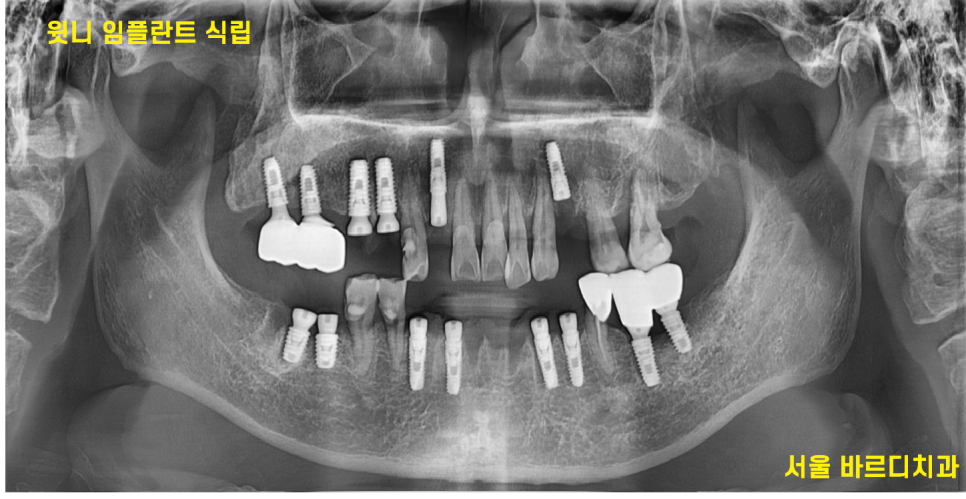

<수술 과정 2>

240508

아래 치료를 끝낸 후

윗니 임플란트 4개를 식립하였습니다.

결론적으로는 하루에 10개 임플란트를 심은 것이죠.

개수가 많아도 실제 수술시간은 1시간이 총 안됩니다.

내비게이션 임플란트 방식을 사용하여

수술을 예측하고 진행하기 때문에

시간이 오래 걸리지 않습니다~